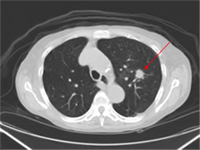

Plan

Radiosurgery plan ablating (treating to extremely high focal radiation dose) lung tumor.

Mrs. King – Stereotactic Radiotherapy/Radiosurgery for lung tumor

A 71-year old otherwise healthy active swimmer recently began experiencing dry cough after swims. Scans and biopsy confirmed an isolated early stage lung cancer. Despite her good health, patient did not wish to consider chest surgery.

For patients with early stage lung cancer, advanced high dose and highly focused radiation therapy can achieving excellent cure rates comparable to surgery, representing a non-invasive therapy with minimal risks and side effects

An advanced radiation technique termed stereotactic radiotherapy/radiosurgery was customized for Mrs. King. This allowed the curative treatment of his tumor, while minimizing radiation dose and side effect risks to the heart, esophagus, and lungs.

She tolerated therapy well and continued swimming during and after therapy.